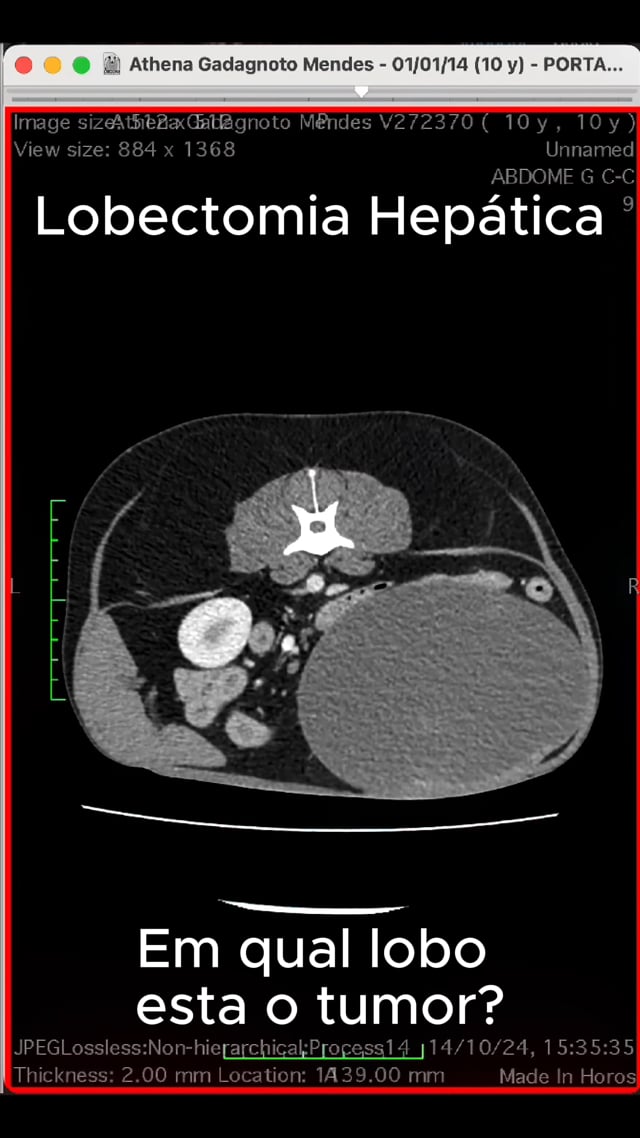

Palestras sobre planejamento cirúrgico por TC e desafios em procedimentos torácicos.

Palestra 'Desafios cirúrgicos: tumores hepáticos' no Animal Health Expo+Congress.